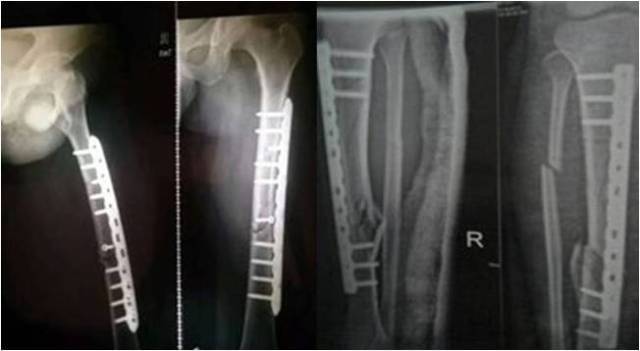

过去的很多年里,为达到解剖复位,手术时采取大切口,广泛显露,骨块血运破坏大,出现了很多骨折愈合慢或不愈合的情况,不得不再次或多次手术,患者非常痛苦。随着观念的改变,微创理念深入人心,手术已经不再是大刀阔斧的时代了。切口一般较小,骨折断端一般不显露,这样可以尽量不加重骨折部位的损伤,有利于骨折愈合。患者功能恢复快,痛苦少。因此,正确的做法是在充分保护断端血供的前提下,争取解剖复位。但不能以破坏断端血供为代价来强求解剖复位,这样得不偿失,此时满足功能复位条件即可接受。

1.骨折部位的旋转移位、分离移位必须完全矫正。

2.缩短移位在成人下肢骨折不超过1cm;儿童若无骨骺损伤,下肢缩短在2cm以内,在生长发育过程中可自行矫正。

3.成角移位:下肢:轻微地(成人不超过10度,儿童不超过15度)向前或向后成角,与关节活动方向一致,日后可在骨痂改造期内自行矫正。向侧方成角移位,与关节活动方向垂直,日后不能矫正,必须完全纠正。否则关节内、外侧负重不平衡,易引起创伤性关节炎。上肢:肱骨干稍有畸形,对功能影响不大;前臂双骨折则要求对位、对线均好,否则影响前臂旋转功能。关节内骨折需解剖复位。

4.长骨干横形骨折,骨折端对位至少达l/3左右,干骺端骨折至少应对位3/4左右。